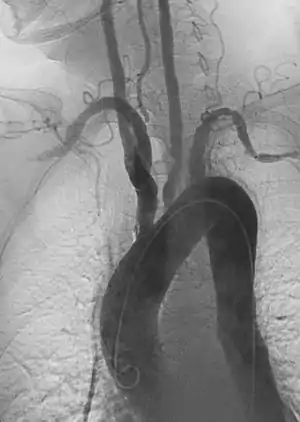

Basics of vascular intervention

Since its development by Charles Dotter when he did a percutaneous peripheral vascular revascularization procedure for the first time on January 16, 1964, on Laura Shaw, Vascular & Interventional Radiology (commonly Interventional Radiology or IR) distinguished itself from earlier approaches to vascular disease by the use of medical imaging to guide endovascular therapies (fixing this from inside the vessel).[75][76] The Seldinger technique is the basic principle that underlies endovascular procedures. Briefly, this involves using a needle to puncture a target vessel, then using a series of small medical guidewires and catheters to pass various tools inside for treatment.[77][78] When these minimally-invasive techniques can be used, patients avoid the need for larger surgical exposure to treat diseased vessels. Though numerous factors can affect patient's post-operative course, in general an endovascular approach is associated with a more rapid recovery time compared to a traditional open vascular surgery.

- Angiography: Sometimes referred to as traditional angiography, catheter angiography or digital subtraction angiography (DSA.) A small needle is inserted into a blood vessel, then exchanged for a catheter over a wire. The catheter is directed at the vessel to be studied, and contrast is directly injected to evaluate the lumen under video X-ray. This is an older technique than modern CT angiography or MR angiography, but provides unique advantages. With a catheter in place, provocative maneuvers can be performed such as breath holds or instillation of vasodilators, to evaluate a patient's blood flow dynamically. This can reproduce symptoms and identify functional abnormalities in a vessel that a static CT or MR imaging cannot.[79][80] Angiography provides the basis for all endovascular therapy.